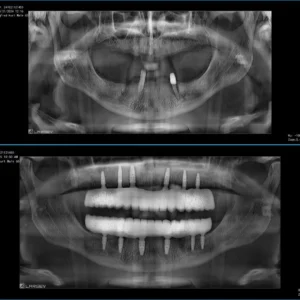

Bazı hastalarda implant planlaması yapılmadan önce Genel Diş Hekimliği muayenesi ile ağız sağlığı detaylı şekilde değerlendirilir. All on 6 implant tedavisinde çene kemiğine yerleştirilen implantlar üzerine sabit diş protezleri uygulanır. Aşağıdaki panoramik röntgen görüntüsünde All on 6 implant tedavisi öncesi ve sonrası durum görülebilir.

All on 6 implant tedavisi öncesi ve sonrası panoramik röntgen görüntüsü

İmplant tedavisinde üst ve alt çeneye yerleştirilen implantlar sabit protezleri destekler ve hastalara doğal görünümlü dişler kazandırır.